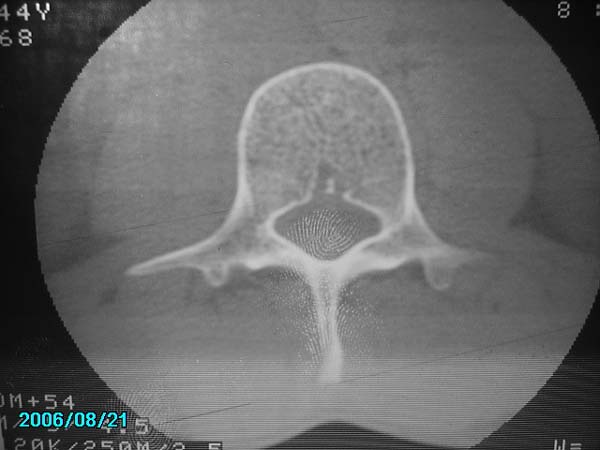

男,40岁,腰疼半年

我还看见了指纹

除有第3-5腰椎椎体后缘中央血管沟显示外,诸椎间盘比较正常。我也象13081830109战友那样看见了指纹,呵呵。